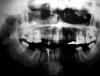

oreshek7 Опубликовано 8 декабря, 2008 Поделиться Опубликовано 8 декабря, 2008 Здраствуйте, я первый раз пришла на этот форум. Прошу помощи. Пришла в клинику с опухолью на десне, сказали свищ. "Инородное тело в гайморовой пазухе", сказал мне стоматолог, выяснилось случайно при панорамном снимке в стоматологии, сделанном до лечения именно в этой клинике. Врач уверил, что это не от зуба. Интернет говорит об обратном, много случаев. Светится как пломбировочный материал. Почистили каналы, положили лекарство, запломбировали. Опухоль на месте. Снимок прилагаю. Очень жду ответов! Ссылка на комментарий

Нск Опубликовано 8 декабря, 2008 Поделиться Опубликовано 8 декабря, 2008 Качество снимка, увы, не очень. Вам, желательно, взять флэшку, отдать в клинику, они на неё скинут Ваш файл, который можно будет уже выложить в данном форуме с хорошим качеством. Ссылка на комментарий

Bier Опубликовано 8 декабря, 2008 Поделиться Опубликовано 8 декабря, 2008 16 зуб? удалять его надо. А снимок то сделан был до лечения? Ну значит это не они вам материала в пазуху ввели. Ссылка на комментарий